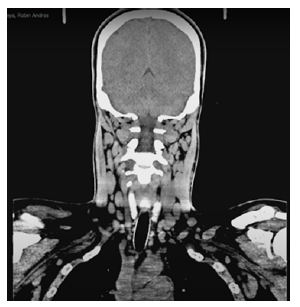

Furthermore, CAT scans of the thorax, neck, PNS and abdomen were performed that same day, revealing multiple bilateral axillary lymphadenopathies (Figure 2), suspicious malignant lymph nodes in the neck, mucosal thickening and opacification of ethmoidal and bilateral maxillary PNS cells with gas bubbles, obstruction of the osteomeatal complex (Figure 3), splenomegaly, and retroperitoneal lymphadenopathies.

Computed axial tomography of the neck, coronal plane in soft tissue window with multiple cervical lymphadenopathies.

Figure 2: Computed axial tomography of the neck, coronal plane in soft tissue window with multiple cervical lymphadenopathies.

Source: Image obtained while conducting the study.